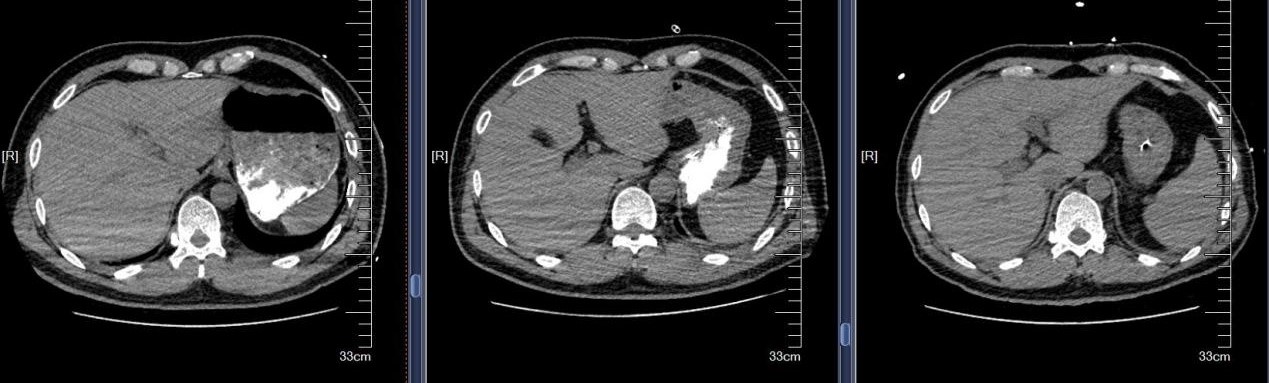

近日,苏州大学附属第四医院成功救治一例极其罕见的支气管异物危机案例。患者是一名48岁男性,因全身被水泥覆盖,伴有意识不清、呼吸困难等危急症状。紧急送医至我院后,CT检查发现其气管和双侧主支气管内充满大量高密度泥沙状异物,同时伴有多发肋骨骨折及腰椎骨折等严重外伤。面对如此复杂的病情,苏大附四院呼吸与危重症医学科蒋军红主任率领团队迅速制定了精准救治方案,成功挽救患者生命。

水泥作为化学性异物,除了造成机械性呼吸道阻塞,还会引发严重的化学性肺炎和呼吸衰竭。患者到院时已出现意识不清、呼吸困难等危重症状,气道清理成为抢救的首要目标。我院蒋军红主任凭借丰富的临床经验和技术优势,带领团队展开了一场与时间竞速的生命营救。

首次支气管镜清除手术:解决大块异物阻塞。因患者颈部有损伤,未行硬镜置入,在麻醉手术科的密切配合下,为患者经口插入8.5号气管插管,接呼吸机辅助通气,建立稳定的呼吸通道。随后,气管镜顺利进镜,发现气管及左主支气管内充满泥沙样分泌物、黄脓痰及块状异物。随后,实行精准操作:用吸引器清除泥沙样物质及黄脓痰;使用活检钳分次取出左下叶大块石状异物,并配合取石网篮清理;刷检带出细小碎石,并进行多部位生理盐水灌洗,最大限度清除可见异物。